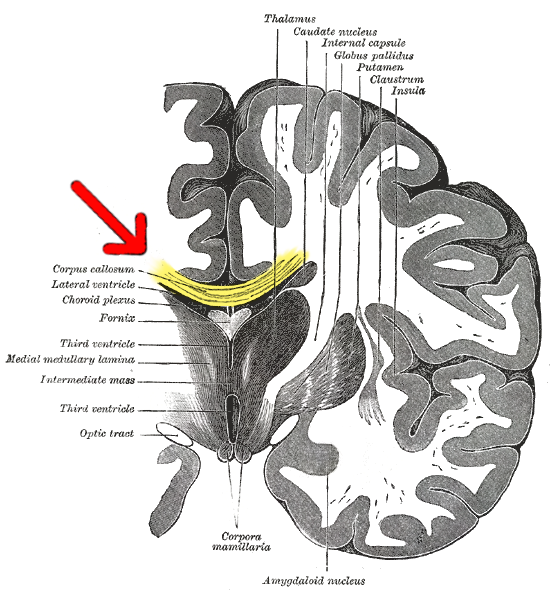

Comme vous vous souvenez peut-être, le cerveau est composé de deux hémisphères: le droit et le gauche, et le corps calleux est le faisceau de neurones reliant les deux. La callosotomie, qui est la section du corps calleux, est une procédure utilisée pour soulager les symptômes chez les patients atteints d’épilepsie grave. Le but de cette procédure est d’inhiber la communication entre les deux hémisphères afin que, lorsqu’une crise commence dans un hémisphère, elle ne puisse pas se propager à l’autre.

Comme vous le savez, les informations de chaque côté du corps vont au côté opposé du cerveau, connu sous le nom d’organisation controlatérale du cerveau. Lorsque le stimulus est représenté sur la moitié droite de l’écran, les informations sont transmises à l’hémisphère gauche. Le centre de la parole étant situé dans l’hémisphère gauche, dans le cerveau de la plupart des gens, le patient peut nommer le stimulus. D’autre part, lorsque le stimulus est représenté sur le côté gauche de l’écran, les informations sont transmises à l’hémisphère droit, où il n’y a pas de centre de la parole, il n’est donc pas possible de nommer le stimulus.